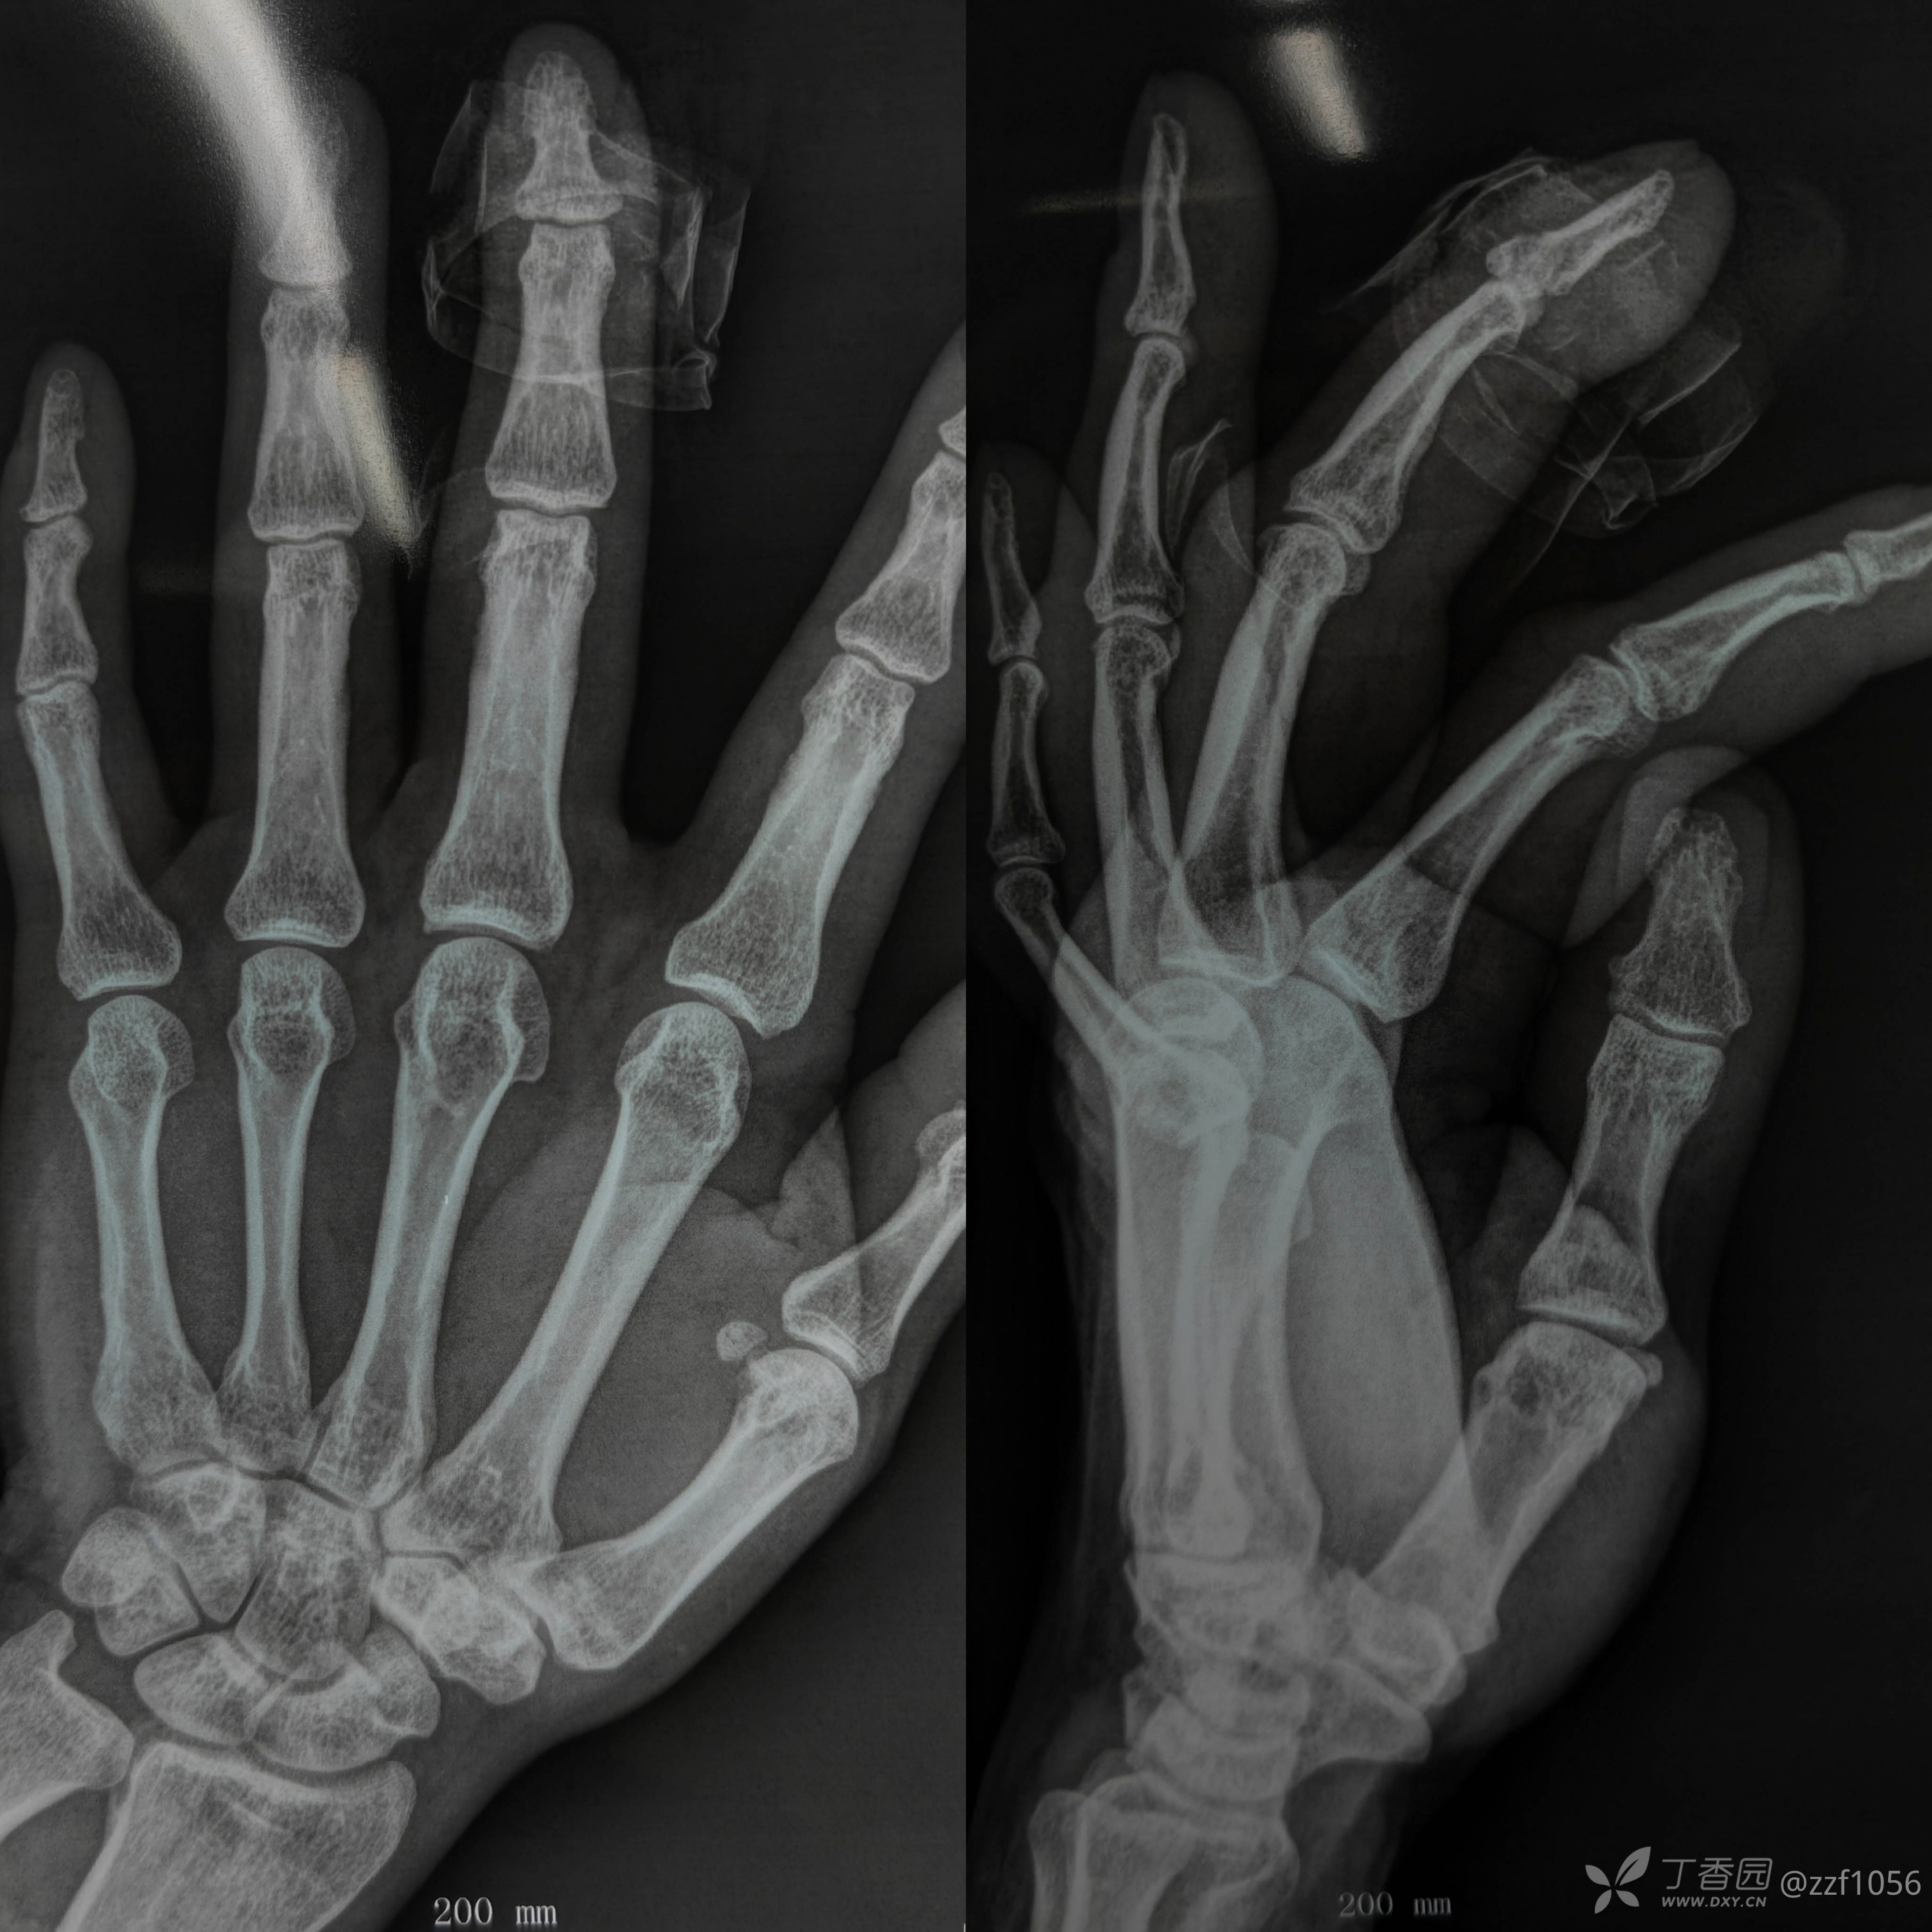

患者张某,男,57岁,左手中指外伤急诊手术

末节指骨基底粉碎骨折

指甲松动,末节畸形